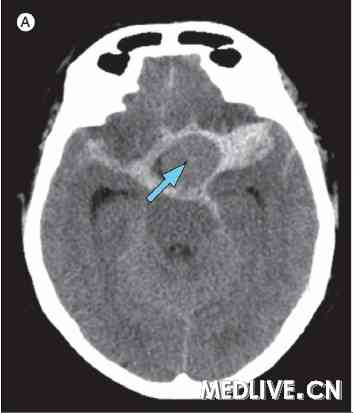

2010年7月, 一名58岁女性被发现晕倒在家中。行气管插管辅助呼吸后转诊至作者所在医院。CT扫描显示,蛛网膜下腔出血且出血源自左颈内动脉一巨大动脉瘤,伴大面积脑肿胀和脑积水(附图A)。

A. 颅脑CT显示源自巨大的左侧颈内动脉瘤处的蛛网膜下腔出血(箭头)